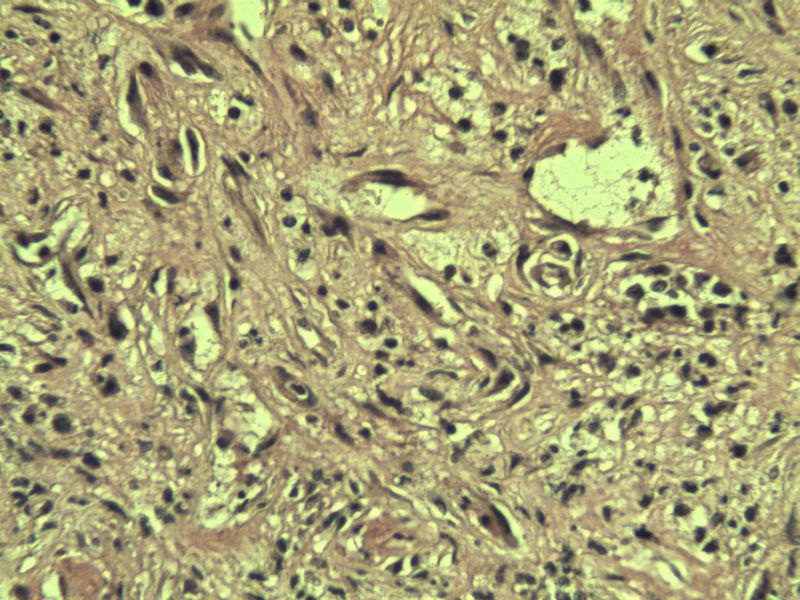

男 33岁 右手食指赘生物5个月 破溃流血一周 灰红不整形组织一块,体积 0.8 × 0.6 × 0.5 cm3。切面灰红,实性,质中。请各位老师看看 是什么? 谢谢了!